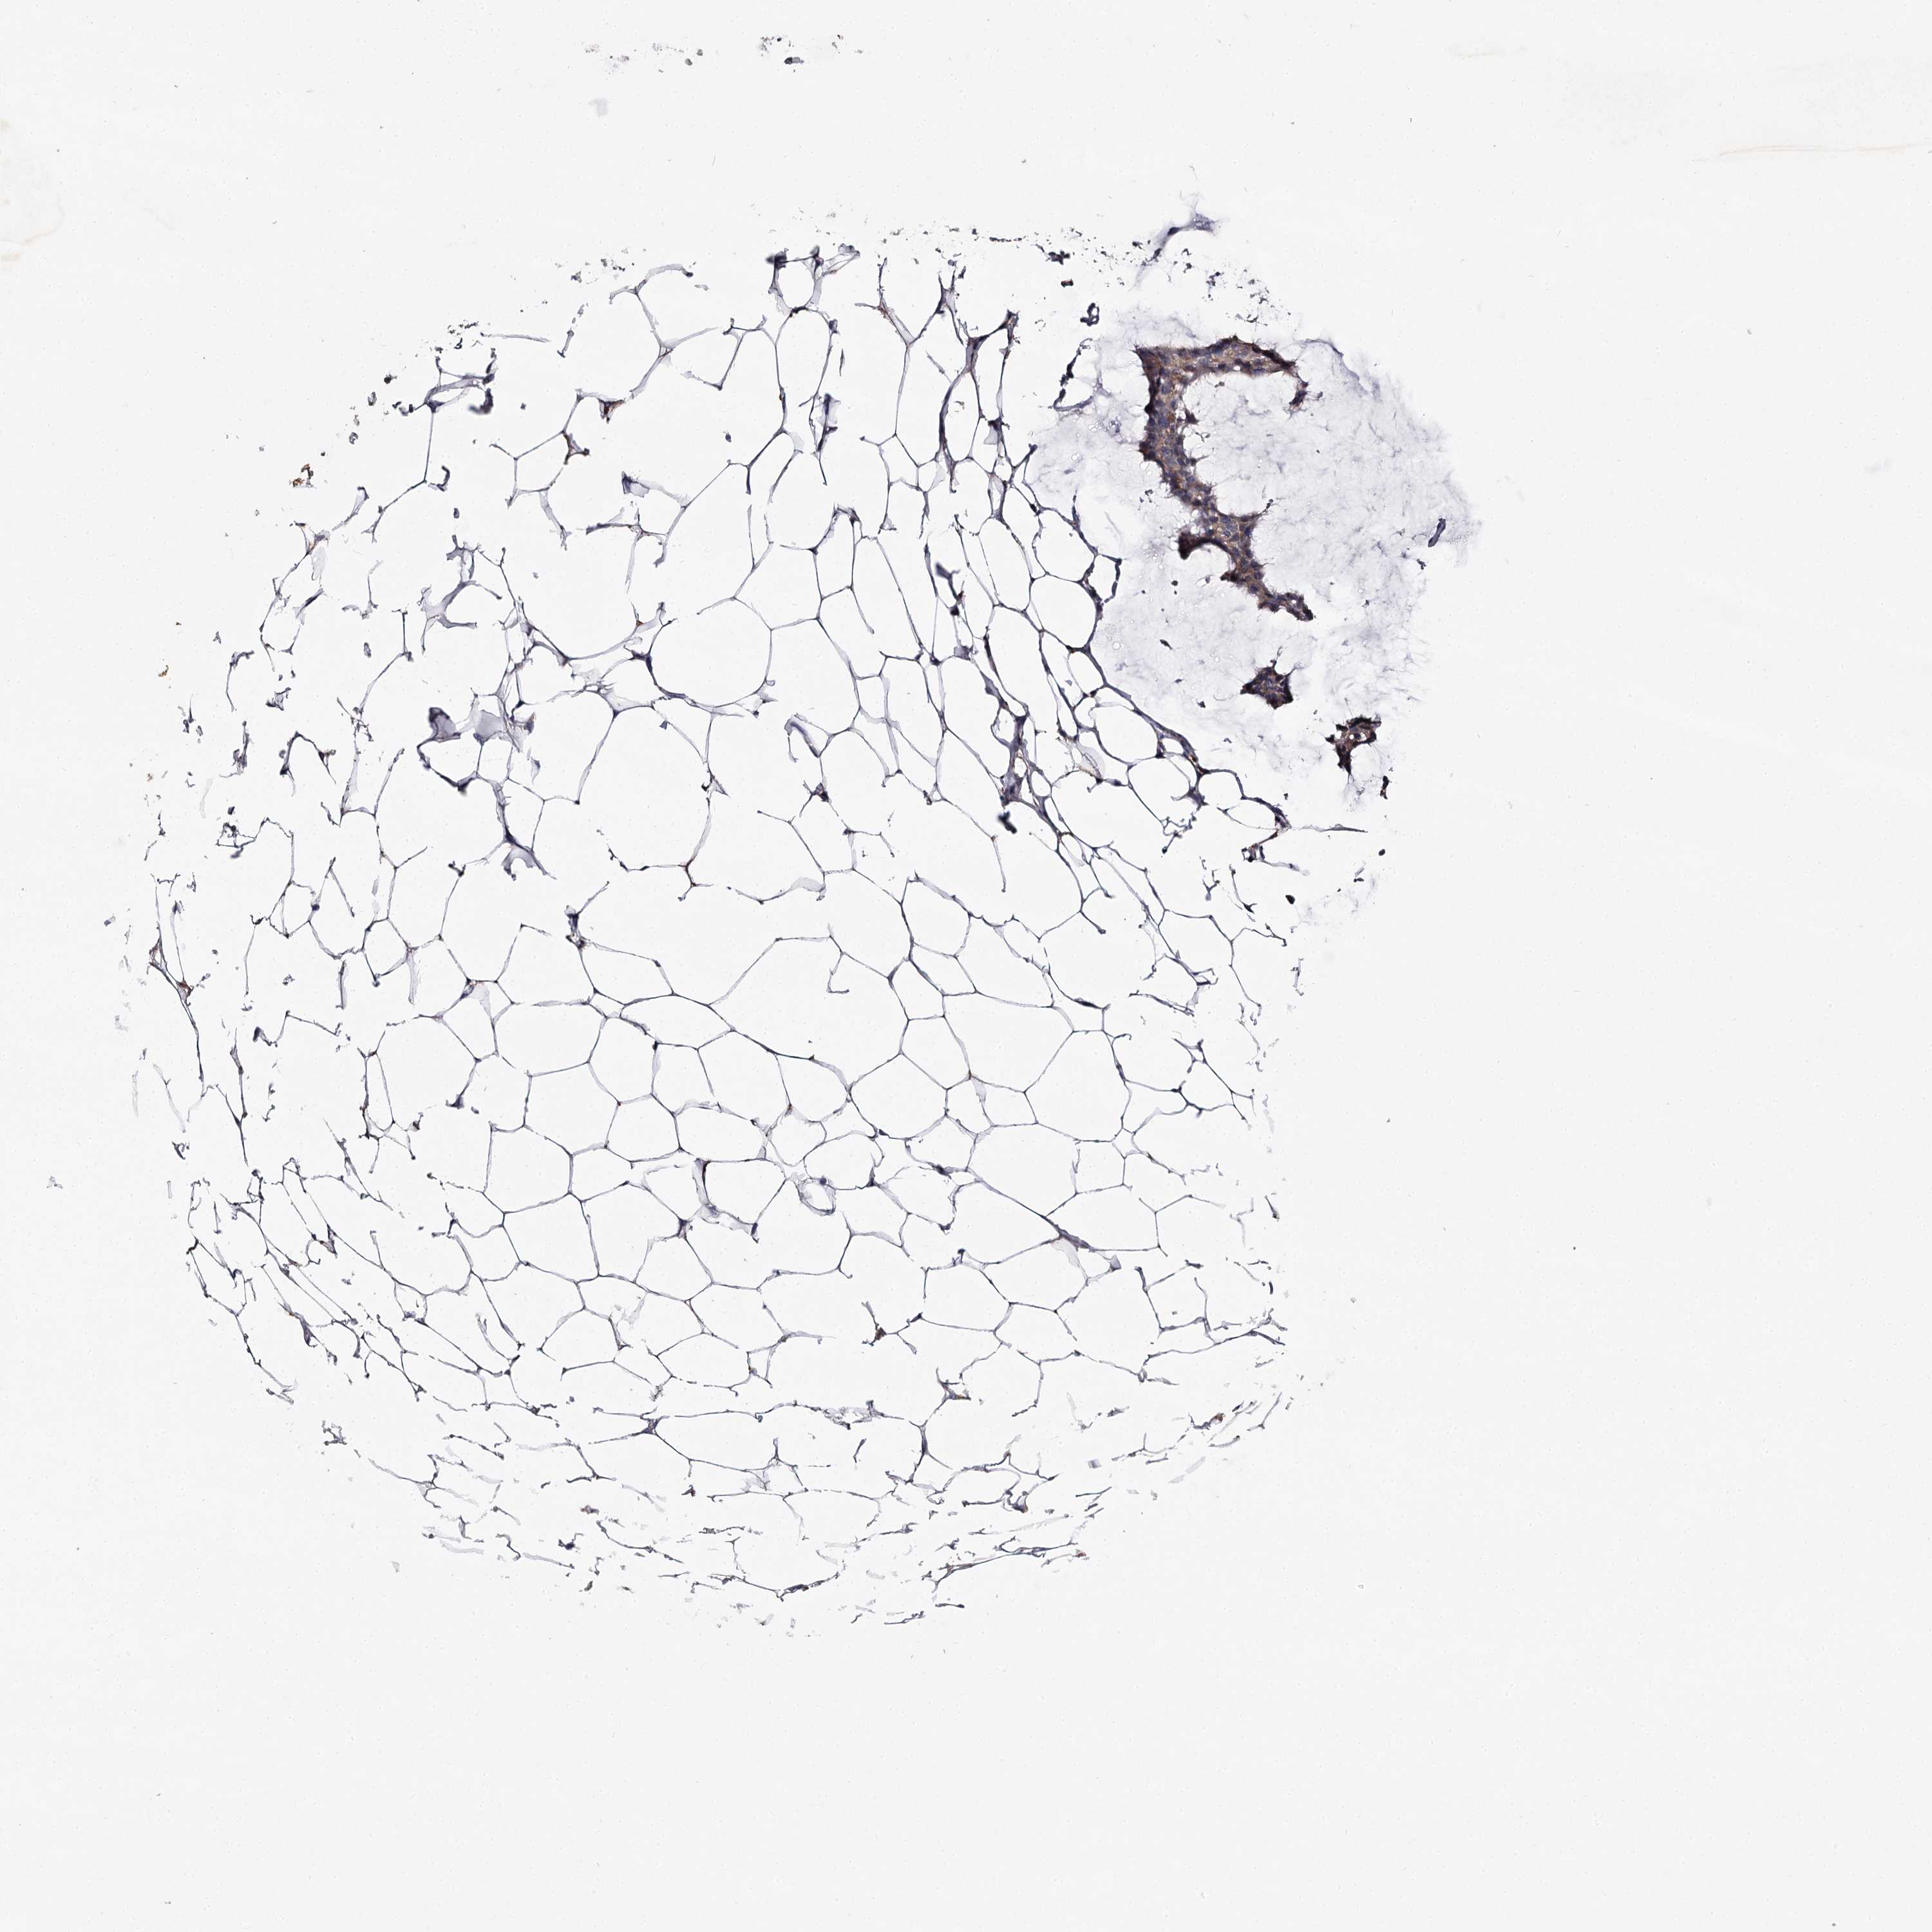

Breast cancer

Human cancer